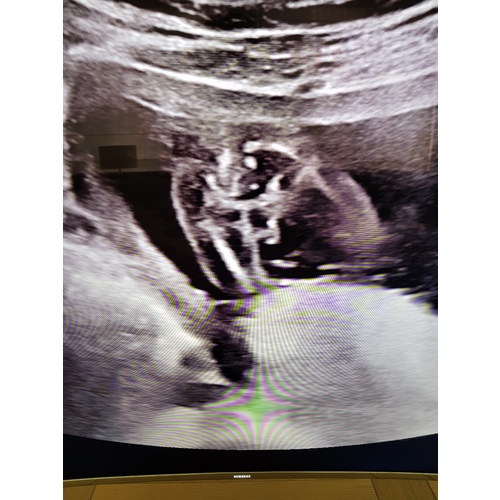

Wat denken jullie een meisje of jongen. Mijn gevoel zelf zegt sterk een jongen. De echo is van 13 weken